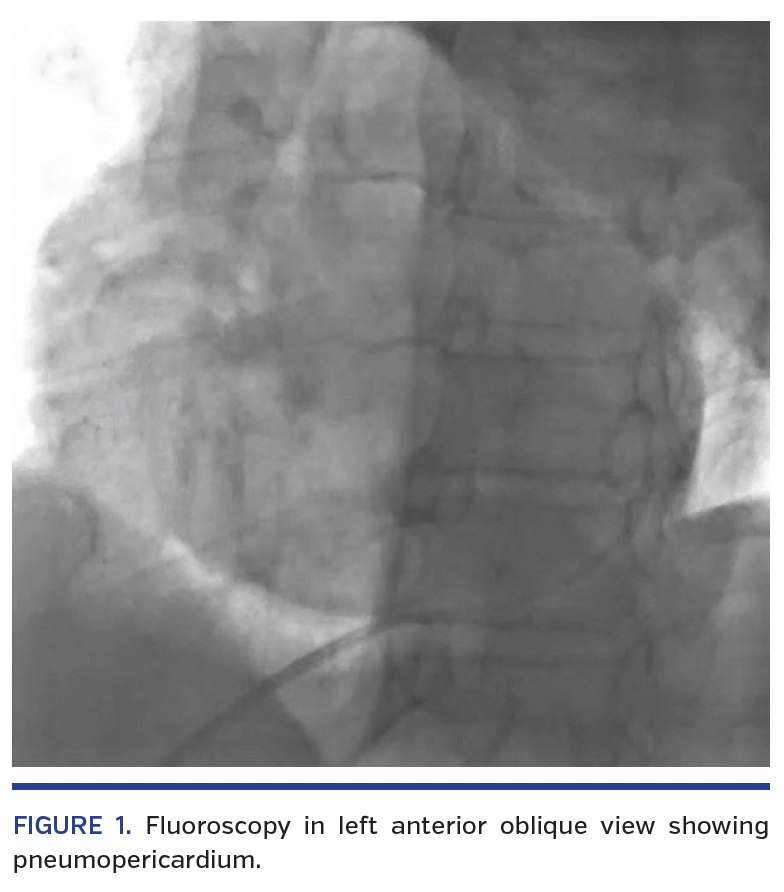

Emergent pericardiocentesis was performed by fluoroscopy-guided subxiphoidal approach. In the catheterization laboratory, a 7 Fr sheath was used to access the pericardial cavity using an over-the-wire technique. A 6 Fr pigtail was inserted through the 7 Fr sheath, following which 540 mL of blood were aspirated by pericardiocentesis. Concomitant blood transfusion was started. Blood pressure started improving and tachycardia settled. However, 5 minutes later, the patient again developed breathlessness with fall in systemic pressures. The transthoracic echocardiographic window became abruptly poor, with poor visualization of cardiac structures. Fluoroscopy was done immediately, which showed presence of air in the pericardial cavity (Figures 1 and 2; Videos 1 and 2). The side port of the 7 Fr sheath was accidentally opened and air was sucked into the pericardial cavity causing pneumopericardium and hemodynamic compromise. Closure of the side port followed by immediate aspiration of the air was performed (Figures 3 and 4; Videos 3 and 4). The patient became hemodynamically stable thereafter.